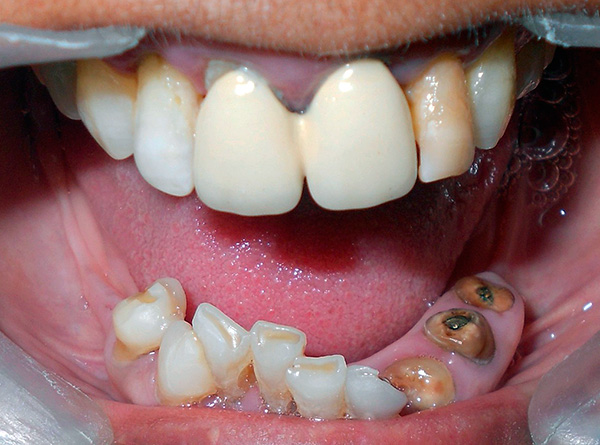

Na foto - periimplantite (inflamação do osso e tecidos moles na área do implante):

É por isso que você não deve confiar cegamente na publicidade de clínicas odontológicas que oferecem implante basal - você deve necessariamente pesar os prós e contras, verificar os atestados médicos e observar os resultados de suas habilidades práticas (por exemplo, examine fotos com exemplos mostrando a cavidade oral dos pacientes antes e depois do tratamento) .